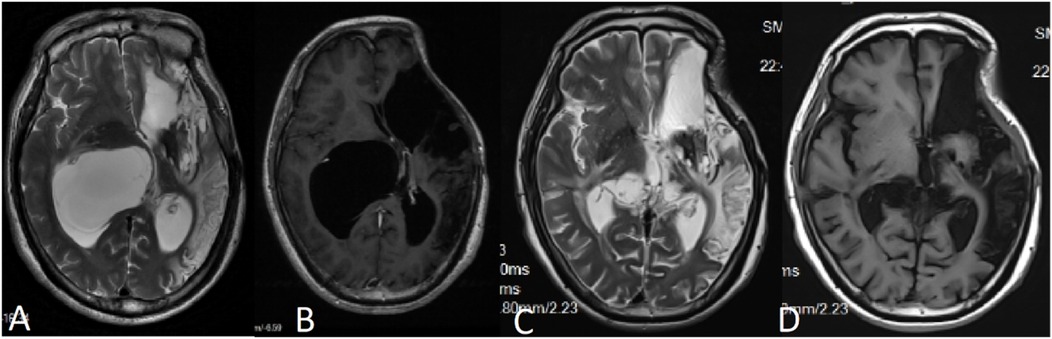

A 50-year-old male patient was admitted with a complaint of a persistent headache lasting for three hours. His medical history was notable for a 20-year history of smoking, with no evidence of hypertension or diabetes. Upon physical examination, the patient was found to be alert and oriented, with a Glasgow Coma Scale (GCS) score of 15 (E4V5M6). The pupils were bilaterally isocoric at 3.0 mm and exhibited intact light reflexes. Signs of meningeal irritation were absent, and no significant neurological deficits were detected. Cranial computed tomography (CT) and computed tomography angiography (CTA) revealed a subarachnoid hemorrhage and an aneurysm of the left internal carotid artery at the ophthalmic segment (Figures 1A,B). He was classified as Hunt-Hess grade II and modified Fisher grade III. The patient underwent a craniotomy for aneurysm clipping. The initial postoperative CT scan of the head demonstrated post-clipping alterations and a marked reduction in the intracranial hematoma relative to prior imaging (Figure 1C). Following this, the patient was administered continuous lumbar drainage of hemorrhagic cerebrospinal fluid (CSF) in conjunction with appropriate supportive care. Three weeks postoperatively, the patient demonstrated a favorable recovery and was discharged without complications. However, 10 days after discharge, the patient was readmitted in a state of sudden coma. The left pupil was noted to be dilated with an absent light reflex. An emergency cranial CT scan revealed the formation of a hematoma in the left frontotemporal lobe, indicating the possibility of rebleeding at the surgical site (Figure 1D), the patient underwent an emergency craniotomy for the evacuation of a hematoma. Intraoperative exploration revealed a recurrent and reruptured aneurysm located in the ophthalmic segment. Successful aneurysm clipping was achieved, along with hematoma evacuation and decompressive craniectomy (Figure 1E). The procedure was completed without complications. After an uncomplicated clinical recovery, the patient was discharged. The pre-discharge follow-up cranial CT scan showed postoperative changes in the brain, with no other significant abnormal findings observed (Figure 1F). Fifteen days post-discharge, the patient exhibited cognitive decline and left-sided weakness. A readmission cranial CT scan revealed a cystic lesion located dorsal to the right ambiens cistern and medial to the parahippocampal gyrus (Figure 2A). Serial imaging conducted at a three-month interval demonstrated progressive enlargement of the cystic lesion (Figure 2B). Subsequent cranial magnetic resonance imaging (MRI) excluded the presence of gliomas and cholesteatomas (Figures 2C,D). One year later, amidst ongoing neurological deterioration, follow-up cranial CT indicated further expansion of the cystic lesion, accompanied by a significant mass effect (Figures 3A,B). Neuroendoscopic exploration was conducted under general anesthesia, during which a cortical fenestration of the temporal lobe was created to facilitate access to the cystic cavity. Intraoperative observations revealed a thickened cyst wall under high tension with evidence of vascular proliferation. The cystic fluid was colorless and transparent, lacking hemosiderin deposition (Figures 4A–C). An arachnoid cyst was suspected intraoperatively, prompting partial resection of the cyst wall and the creation of a lateral ventriculostomy. The fistulous opening measured approximately 2.5 cm in diameter, facilitating communication with the lateral ventricle (Figure 4C). Histopathological analysis of the cyst wall confirmed the diagnosis of an arachnoid cyst (Figure 5). Following the surgical procedure, the patient demonstrated a gradual enhancement in left-sided motor weakness and cognitive abilities. At the three-month follow-up, both motor and cognitive functions had nearly returned to baseline levels. The GCS score was recorded at 15 (E4V5M6). The latest cranial MRI revealed a substantial reduction in cyst volume, accompanied by a complete resolution of the mass effect (Figures 3C,D).

Figure 3. (A,B) MRI conducted 12 months post-craniotomy revealed a further enlargement of the arachnoid cyst accompanied by a significant mass effect, resulting in noticeable compression of the thalamus. (C,D) Six months following the partial resection of the cyst wall, MRI findings indicated a reduction in the mass effect exerted by the cyst, with no evidence of recurrence.